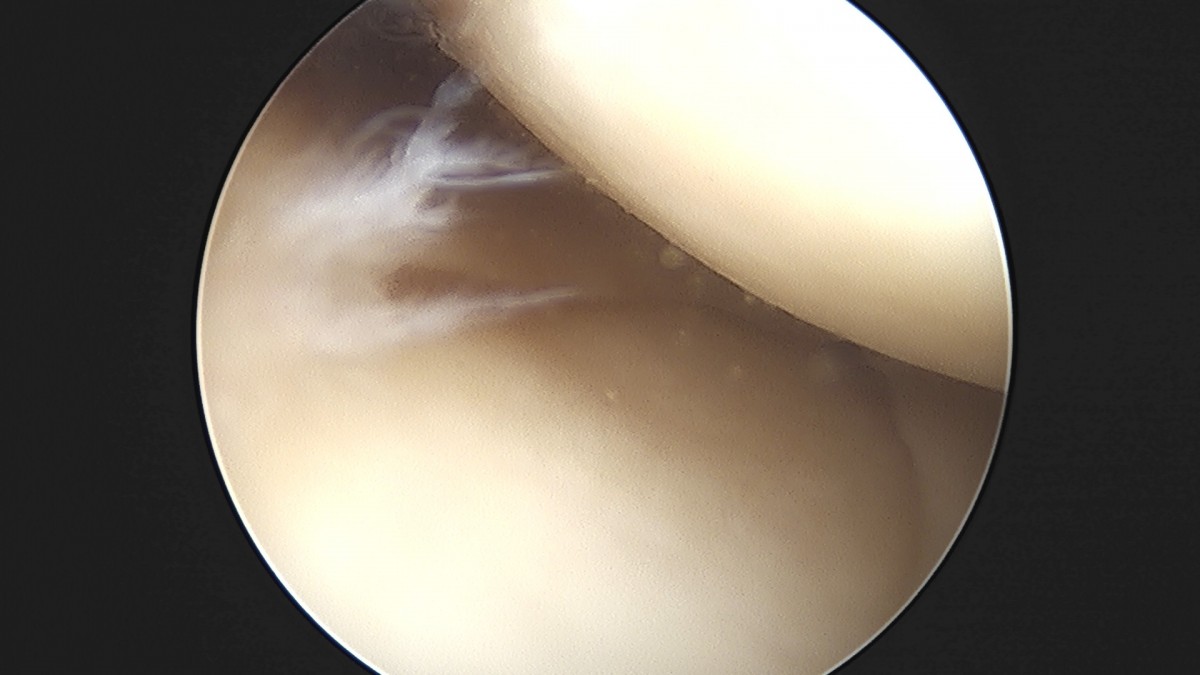

이재상원장님 무릎 반월상 연골판 절제술 조미O 환자

작성자 최고관리자 댓글 0건 조회 368회 작성일 25-09-16 16:01